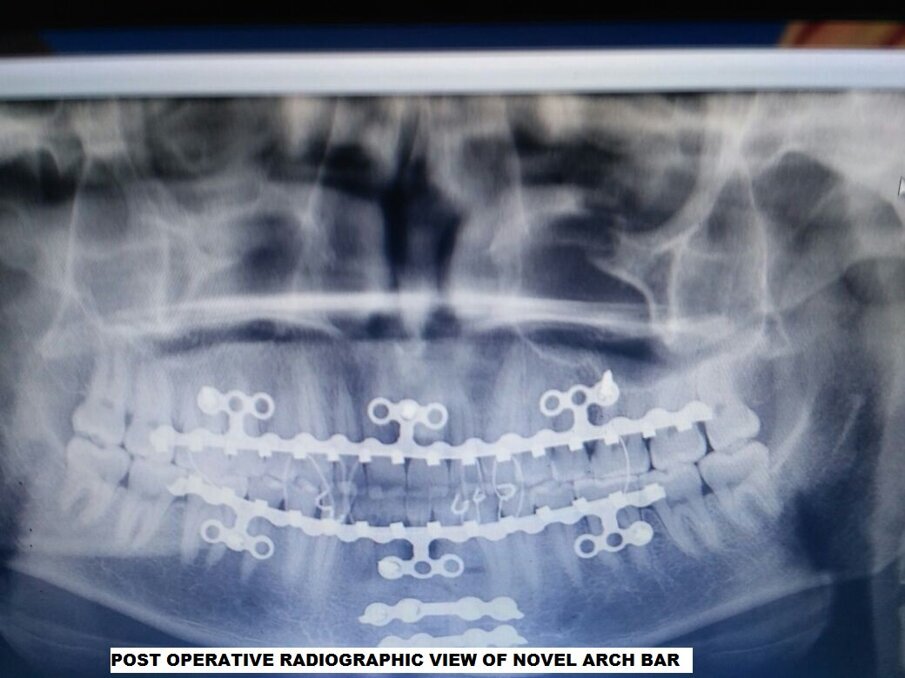

Fig 2: Post-op radiographic view of Novel Arch Bar

After taking the detailed history, patients and radiograph of patients are thoroughly examined; “Novel Arch Bar” is placed in maxillary and mandibular arch individually and stabilized with an interlocking screw. In each arch, three, 2mm diameter 6mm length interlocking screws are placed through attach gingiva and inserted until the head of the screw is flushed. Two screws are placed bilaterally in the posterior region and one is placed centrally using a 1.5 mm drill under copious normal saline irrigation. Three segments are extended from each arch bar, each segment contains three holes for screw placement, screws can be placed in any hole among the three so as to bypass the fracture line that may cause loosening of a screw or bypass the root of the tooth to prevent the tooth injury. After close reduction of fracture intermaxillary fixation was done with 24 gauge wire.